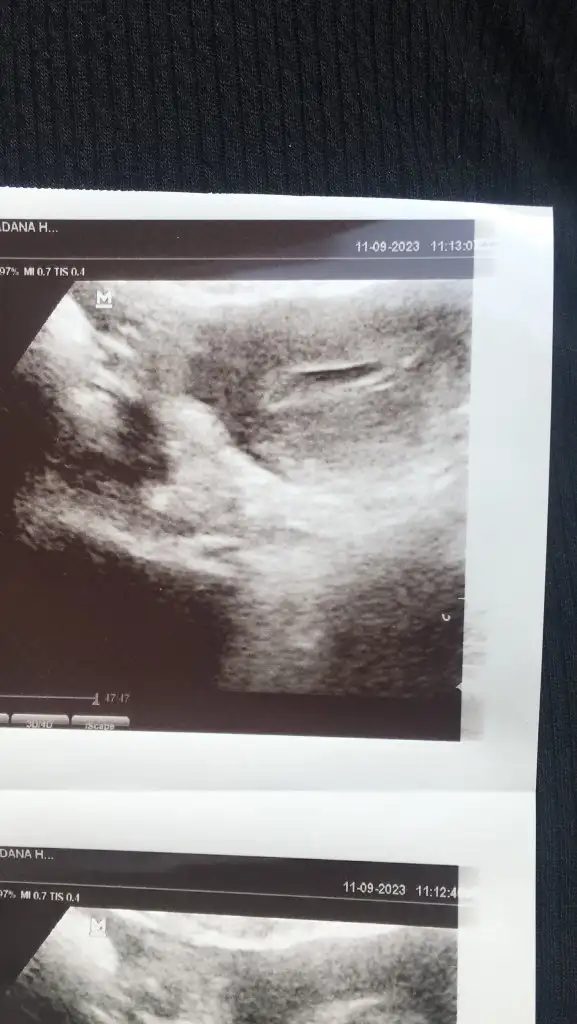

Gittim canım kesenin yanında kanama alanı var düşükle sonuçlanabilir dedi.ilk attıgım kese digeri kanama alanımelegim can bıtanem nasılsın ne yaptın

Evet canım kesenin yanında kanama alanı varmelegim can gittin mi kuzum doktora?

Kuzum bende de vardı. Hatta iki kese demişti hatırlıyor musun bilmiyorum. Ama biri kan pıhtısıymış. İnşallah hayırlısıyla dağlıkla devam etsin. Bir daha ne zaman gideceksin?Evet canım kesenin yanında kanama alanı var

Perşembe yada cuma gel dedi canım. İlki kanama alanı digeri keseKuzum bende de vardı. Hatta iki kese demişti hatırlıyor musun bilmiyorum. Ama biri kan pıhtısıymış. İnşallah hayırlısıyla dağlıkla devam etsin. Bir daha ne zaman gideceksin?

Rabbim ol derse herşey olur canım içini ferah tut Allahın izniyle hiç bişey olmazPerşembe yada cuma gel dedi canım. İlki kanama alanı digeri kese

Canım sakın kötü düşünüp kendini de bebeğini de strese sokma güzelce yat dinlen fazla ayakta kalma hayırlısıyla hiç bişey olmicak iyi olacaksınız ikinizdeGittim canım kesenin yanında kanama alanı var düşükle sonuçlanabilir dedi.ilk attıgım kese digeri kanama alanı

Kuzum kesenın ıcınde bebek olusmaya baslamıs,gordunmu sende gecen gıttıgıne gore fark var.lütfen dınlen bak cocuklarda okula baslamıstır sımdı gerekırse annenden fln yardım ıste bir müddet kalkma canım yat,kavusacaksın bebegıne ben ınanıyorum Allahın ıznıyleGittim canım kesenin yanında kanama alanı var düşükle sonuçlanabilir dedi.ilk attıgım kese digeri kanama alanı